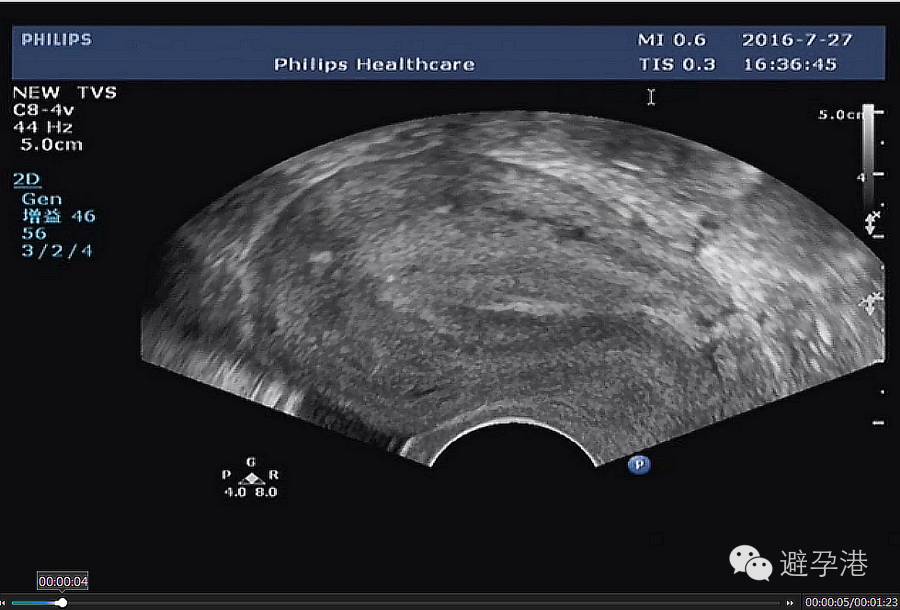

2.分辨率高超声仪器,在子宫肌壁间可见一稍强光点,为吉妮致美线结。

吉妮致美环怎么样吉妮致美节育器超声图像解读_https://www.jmylbn.com_新闻资讯_第4张